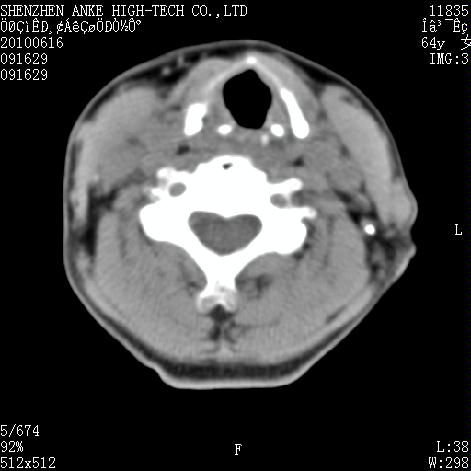

标题: CT27132:患者女,64岁,颈部及全身多处包块,现觉吞咽困难4 [打印本页]

标题: CT27132:患者女,64岁,颈部及全身多处包块,现觉吞咽困难4

右侧甲状腺占位,肿瘤可能性大,癌

右侧甲状腺癌伴右颌下腺淋巴结转移

右侧甲状腺癌伴淋巴结转移

右侧甲状腺癌伴淋巴结转移可能性大

右侧甲状腺癌伴淋巴结转移可能性大。

右侧甲状腺癌伴右颌下腺淋巴结转移!建议增强!